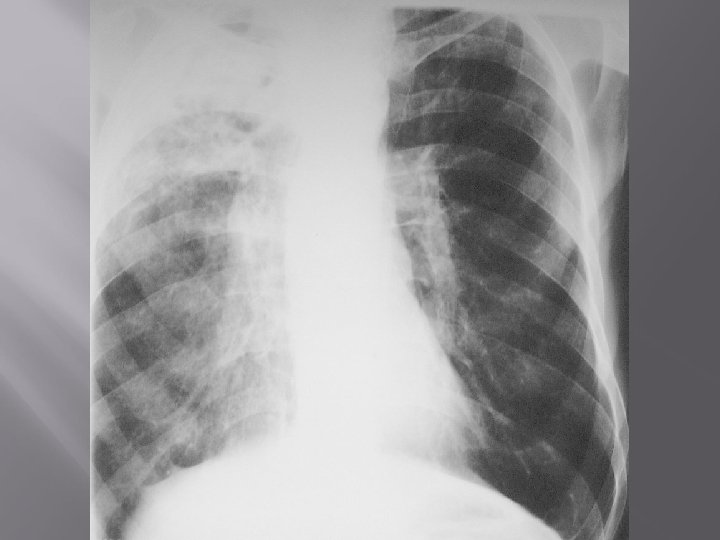

ASPERGILLOMA Saprophytic colonisation of fungi in pulmonary cavities Manifestation No symptoms Haemoptysis Fever Cachexia Chraracteristic x-ray picture! Therapy: surgery